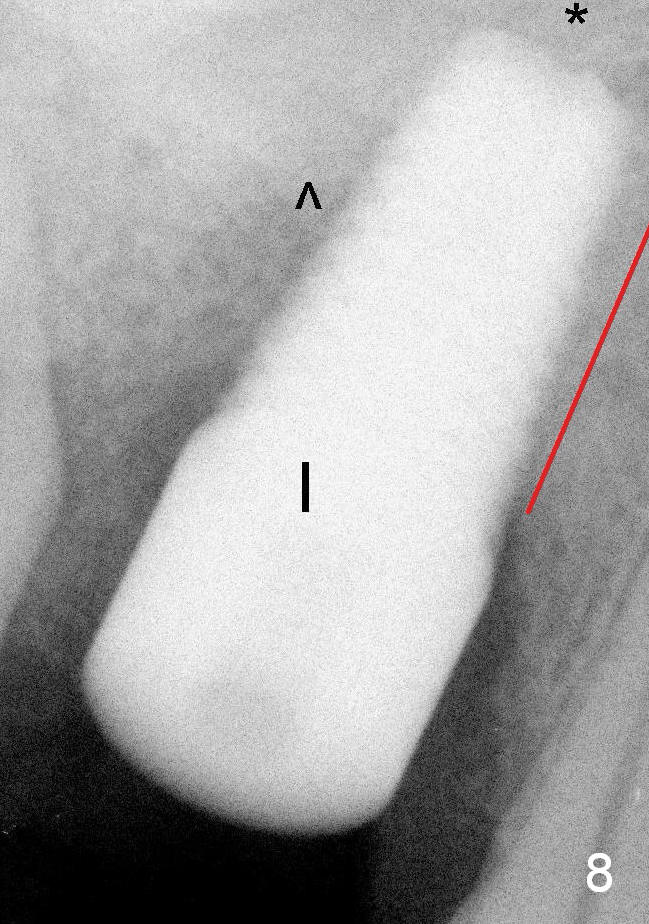

It appears that when a 7x17 mm implant is placed (Fig.8), the bone contact is increased vertically (red line) as the diameter of the implant increases. ^: sinus floor; *: bone present apical to the implant.